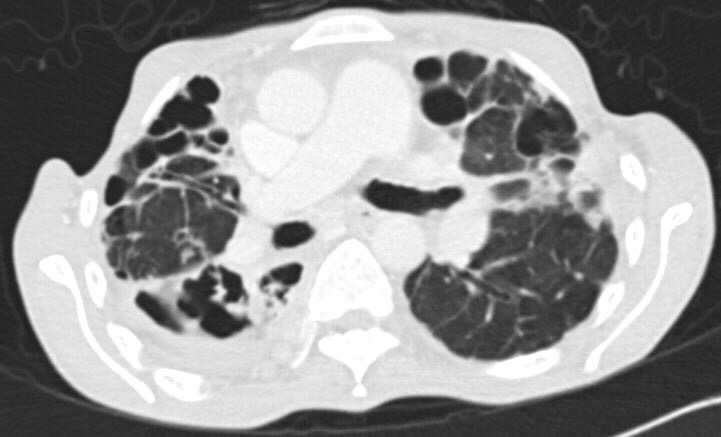

Chest X-ray showed worsening bilateral infiltrates – particularly on the right – and two courses of oral antibiotics (augmentin first followed by ciprofloxacin) produced only transient relief.

Sputum sent for acid-fast bacilli (AFB) smear was positive, and mycobacterial cultures were positive in two weeks for Mycobacterium abscessus. A repeat sputum sample yielded the same result. A CT thorax was performed, showing essentially worsening of bronchiectasis.